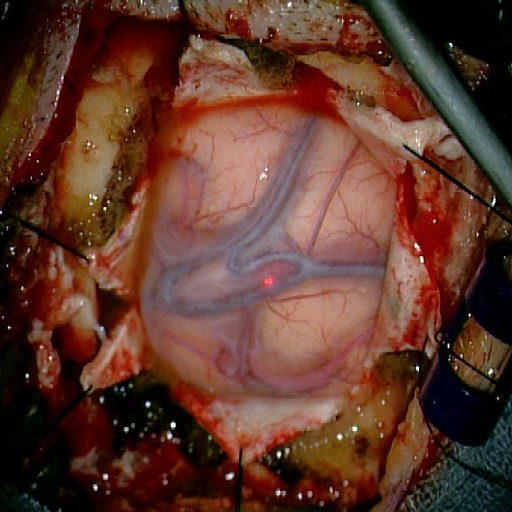

We tested our method retrospectively on 6 clinical datasets from 6 patients (cases) (see Fig. 5). These consisted of preoperative T1 contrast MRI scans and intraoperative images of the brain surface after dura opening. Cortical vessels around the tumors were segmented and triangulated to generate 3D meshes using 3D Slicer. We generated 100 poses for each 3D mesh (i.e.: each case) and used a total of 15 unique textures from human brain surfaces (different from our 6 clinical datasets) for synthesis using . In order to account for potential intraoperative brain deformations [4] we augment the textured projection with elastic deformation [21] resulting in approximately 1500 images per case. The surgical images of the brain (left image of the stereoscopic camera) were acquired with a Carl Zeiss surgical microscope. The ground-truth poses were obtained by manually aligning the 3D meshes on their corresponding images.

Fig. 5 shows our results as Augmented Reality views with bounding boxes and overlaid meshes. Our method produced visually consistent alignments for all 6 clinical cases without the need for initial registration. Because our current method does not account for brain-shift deformation, our method produced some misalignment errors. However, in all cases, our predictions are similar to the ground truth.